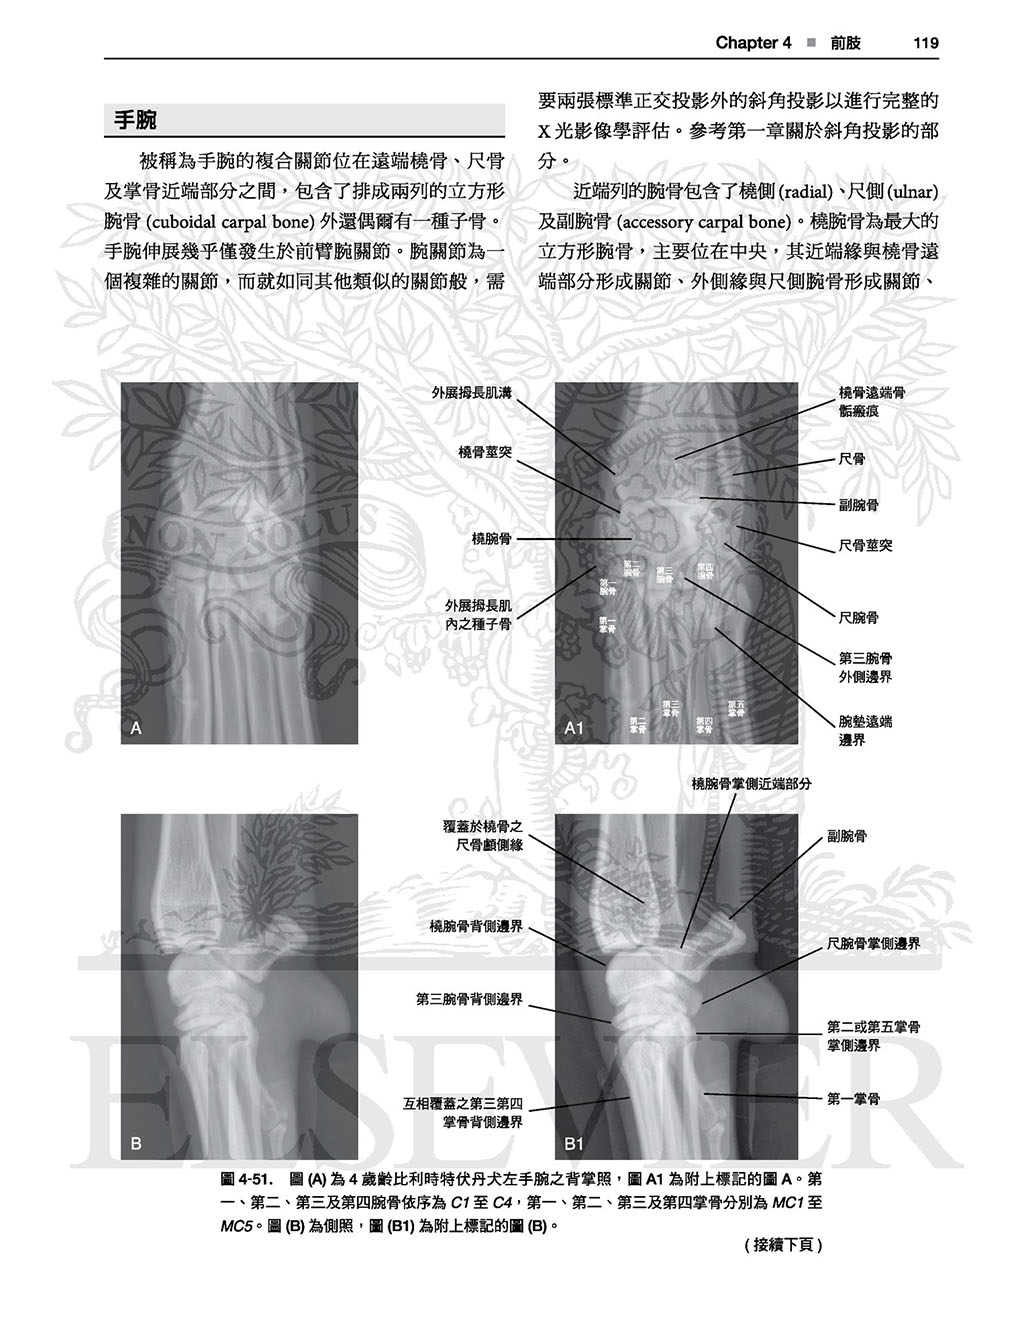

4前肢, 87